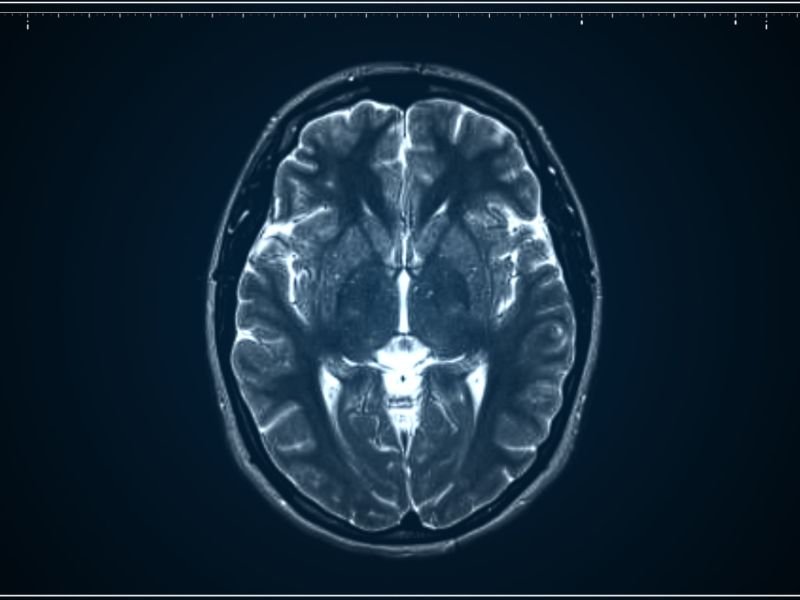

Tratamento Avançado para Enxaqueca em Tubarão A enxaqueca é uma condição neurológica que afeta milhões de pessoas em todo o mundo. Em Tubarão, o tratamento avançado para enxaqueca tem se tornado uma prioridade para muitos